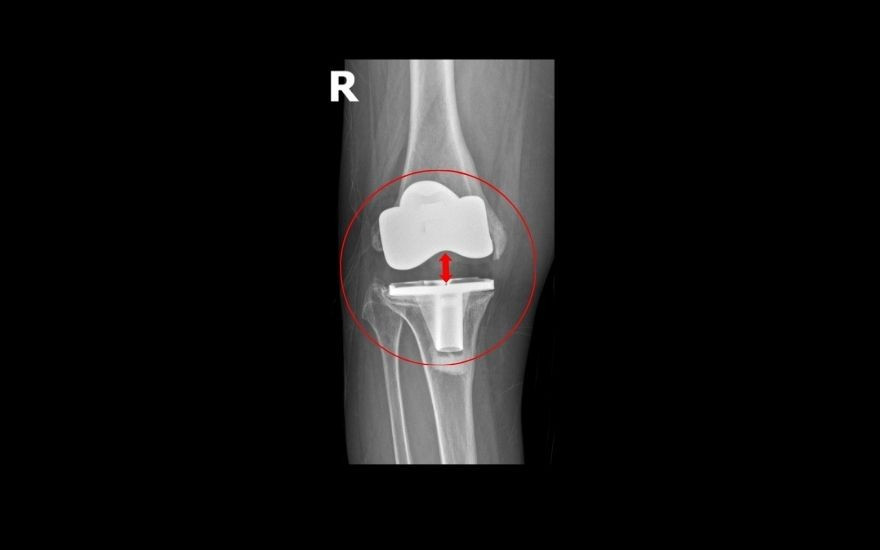

Suốt nhiều tháng, bà Oanh đi khám ở nhiều bệnh viện để tìm hướng điều trị. Dù được nhiều bác sĩ chỉ định phẫu thuật, bà vẫn trì hoãn vì lo ngại rủi ro, chỉ uống thuốc giảm đau và tập phục hồi chức năng nhưng khớp gối ngày càng biến dạng, việc di chuyển cũng phải phụ thuộc vào xe lăn. Qua các phương tiện truyền thông, bà biết đến BVĐK Hồng Ngọc - Phúc Trường Minh có phương pháp phẫu thuật hiện đại và quyết định đến thăm khám. Tại đây, các bác sĩ phát hiện khớp gối nhân tạo của bà đã bị “trôi” khỏi ổ khớp.

Theo TS.BS Lê Quang Huy, Trưởng khoa Ngoại Chấn thương chỉnh hình - Thần kinh sọ não, BVĐK Hồng Ngọc - Phúc Trường Minh: “Trường hợp của bệnh nhân Oanh hiếm gặp. Chỉ sau gần 5 năm phẫu thuật, cấu phần lồi cầu đùi nhân tạo (phần kim loại bao bọc đầu dưới xương đùi) đã lún vào lồi cầu trong xương đùi ~ 2cm, khiến khớp gối lệch khỏi vị trí ban đầu, mất vững kèm mất cân bằng mô mềm quanh khớp dẫn đến bệnh nhân không đi lại được. Các nguyên nhân gây biến chứng như nhiễm trùng hay viêm xương tuỷ đã được chúng tôi loại trừ, có thể do cơ địa bệnh nhân không phù hợp với loại khớp cấy ghép, tình trạng loãng xương nặng gây tiêu xương hoặc kỹ thuật cắt xương chưa thực sự chuẩn xác. Giải pháp duy nhất để phục hồi vận động và ngăn ngừa nguy cơ tàn phế là phẫu thuật thay lại khớp gối”.

Ca mổ của bà Oanh được đánh giá là phức tạp do gân cơ, dây chằng và cấu trúc xương quanh khớp tổn hại nghiêm trọng, đòi hỏi bác sĩ tính toán kỹ lưỡng để vừa khôi phục trục chân nguyên bản, vừa bảo tồn tối đa gân cơ, hạn chế biến chứng tái phát. Sau khi hội chẩn cùng GS. Hiranaka Takafumi (Giám đốc Trung tâm Phẫu thuật Khớp, Bệnh viện Takatsuki, Nhật Bản), TS.BS Lê Quang Huy quyết định loại bỏ khớp nhân tạo cũ, thay thế khớp mới bằng kỹ thuật thay khớp gối gióng trục động học, không cắt gân cơ với đường mổ nhỏ, ít xâm lấn, giúp bệnh nhân ít đau, có thể đi lại sau 1-2 ngày. Ngoài ra, bác sĩ sử dụng khớp bản lề chuôi dài để tăng độ vững, khôi phục trục chân, giúp người bệnh khôi phục chức năng và tầm vận động, hạn chế nguy cơ di lệch khớp.